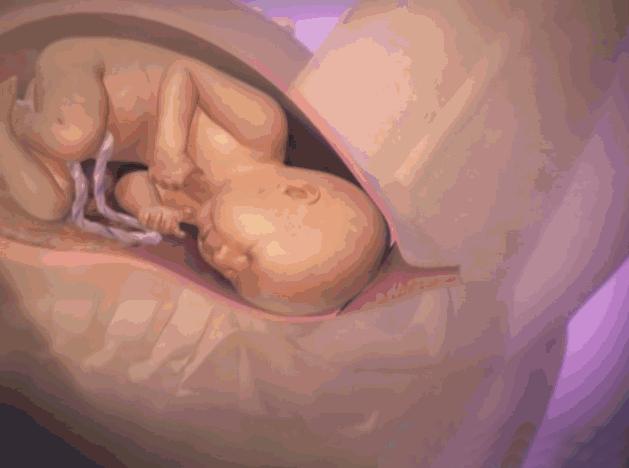

是指怀孕时子宫羊膜腔内的液体。在整个怀孕过程中,它是维持胎儿生命所不可缺少的重要成分。在胎儿的不同发育阶段,羊水的来源也各不相同。在妊娠第一个三月期,羊水主要来自胚胎的血浆成分;之后,随着胚胎的器官开始成熟发育,其他诸如胎儿的尿液、呼吸系统、胃肠道、脐带、胎盘表面等等,也都成为了羊水的来源。

● 在妊娠期,羊水能缓和腹部外来压力或冲击,使胎儿不至直接受到损伤。

● 羊水能稳定子宫内温度,使不至有剧烈变化,在胎儿的生长发育过程中,胎儿能有一个活动的空间,因而,胎儿的肢体发育不至形成异常或畸形。